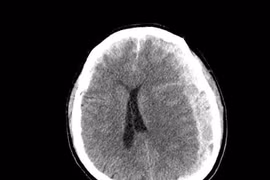

1 giờ sau ngã tại nhà, cụ ông 70 tuổi nhanh chóng hôn mê

Ca bệnh diễn biến rất nhanh, nguy kịch, đòi hỏi quyết định chính xác và phối hợp tức thời giữa cấp cứu, chẩn đoán hình ảnh, phẫu thuật thần kinh.